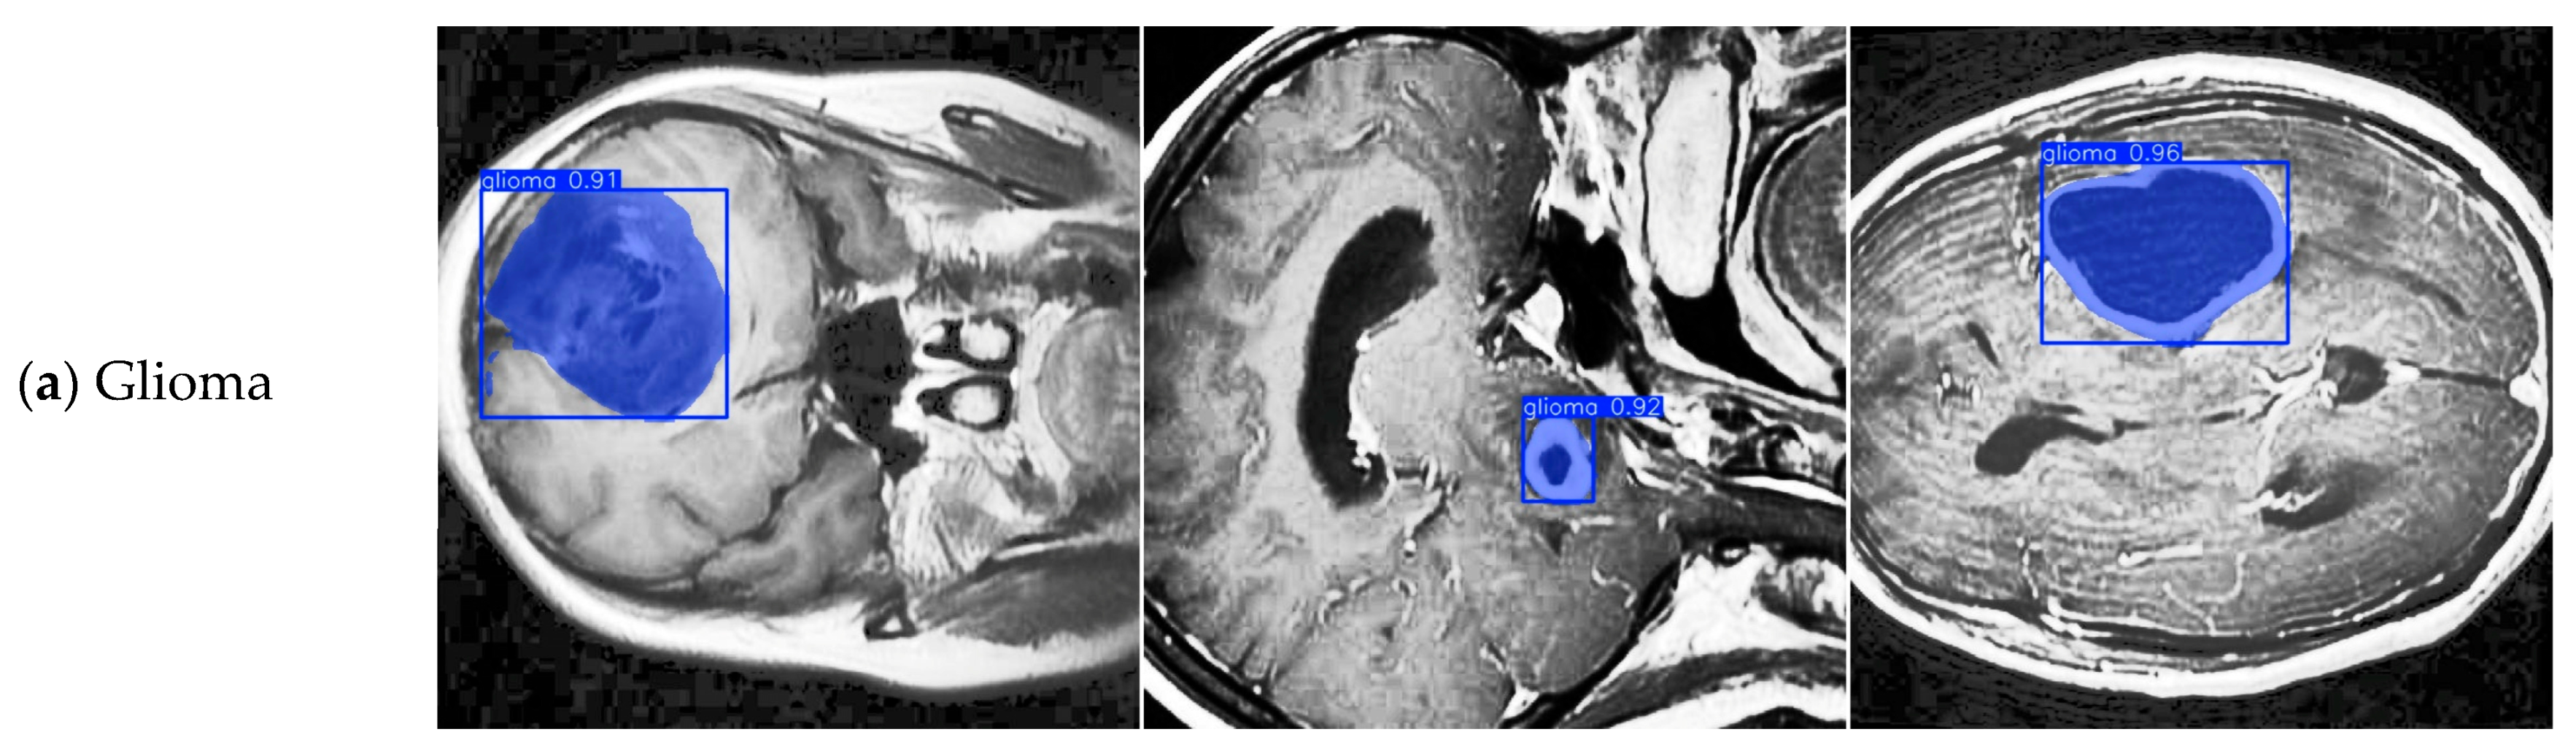

4.8. Discussion on Brain Tumor Classification Ability

- Roboflow. BRAIN TUMOR > Roboflow Universe. Available online: https://universe.roboflow.com/college-piawa/brain-tumor-j0l2c (accessed on 11 September 2025).

| Class | FALS-YOLO Correct Classification | FALS-YOLO Misclassification | YOLOv8-Seg Correct Classification | YOLOv8-Seg Misclassification |

|---|---|---|---|---|

| Glioma | 132 | 40 | 124 | 37 |

| Meningioma | 58 | 10 | 56 | 6 |

| Pituitary | 81 | 10 | 78 | 5 |

| Background | - | 31 | - | 42 |